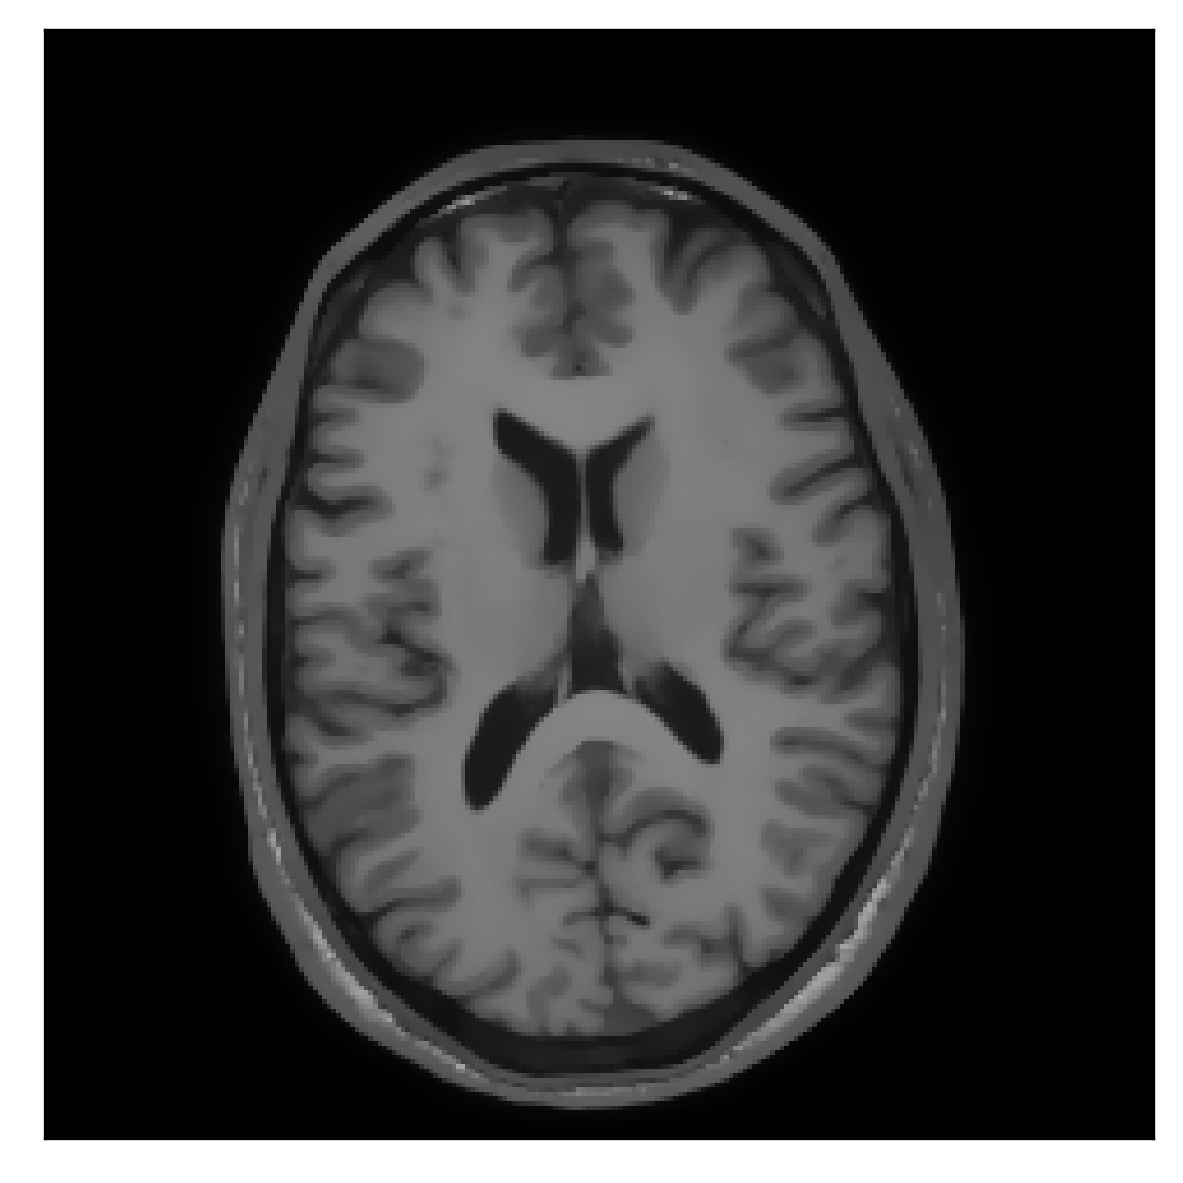

In the first experiment, the corrupted contrast has been acquired with a protocol based on a linear filling pattern in -space. Note that, in this particular case, the scanner reconstruction implements the SENSE method. We then extracted the DICOM of both amplitude and phase produced by the scanner, and used it as input data (after a Fourier transform) for the algorithm. The proposed scheme is able to successfully remove the motion artifacts in Figure 12.

| Section 3.3, Figure 12 | Sagittal | 22.26 | 27.54 | 0.6963 | 0.8409 |

| Coronal | 23.46 | 31.65 | 0.7321 | 0.8370 | |

| Axial | 24.55 | 32.33 | 0.7895 | 0.8144 | |

| Section 3.3, Figure 12 | T2 | Completely corrected | No blurring | No additional artifacts | |